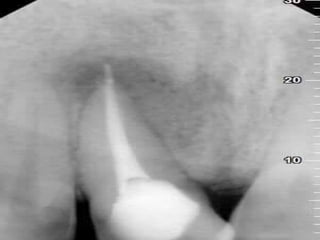

 Radio graphically interruption in lamina

dura Destruction of periapical tissues

SIGNS AND SYMPTOMSSIGNSAND SYMPTOMS  Does not respond to vitality test  Percussion no pain Slight sensitivity to palpation  Radio graphically interruption in lamina dura Destruction of periapical tissues 